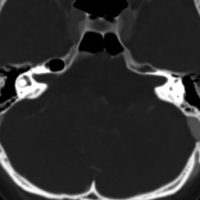

斜台の脊索腫 classical type

CTでは,斜台から左蝶形骨にかけて不規則な骨破壊像がみられます。

骨をみているCTです。鞍背からsphenooccipital synchondrosisまでの斜台骨皮質が失われています。かなり特徴的な所見です。